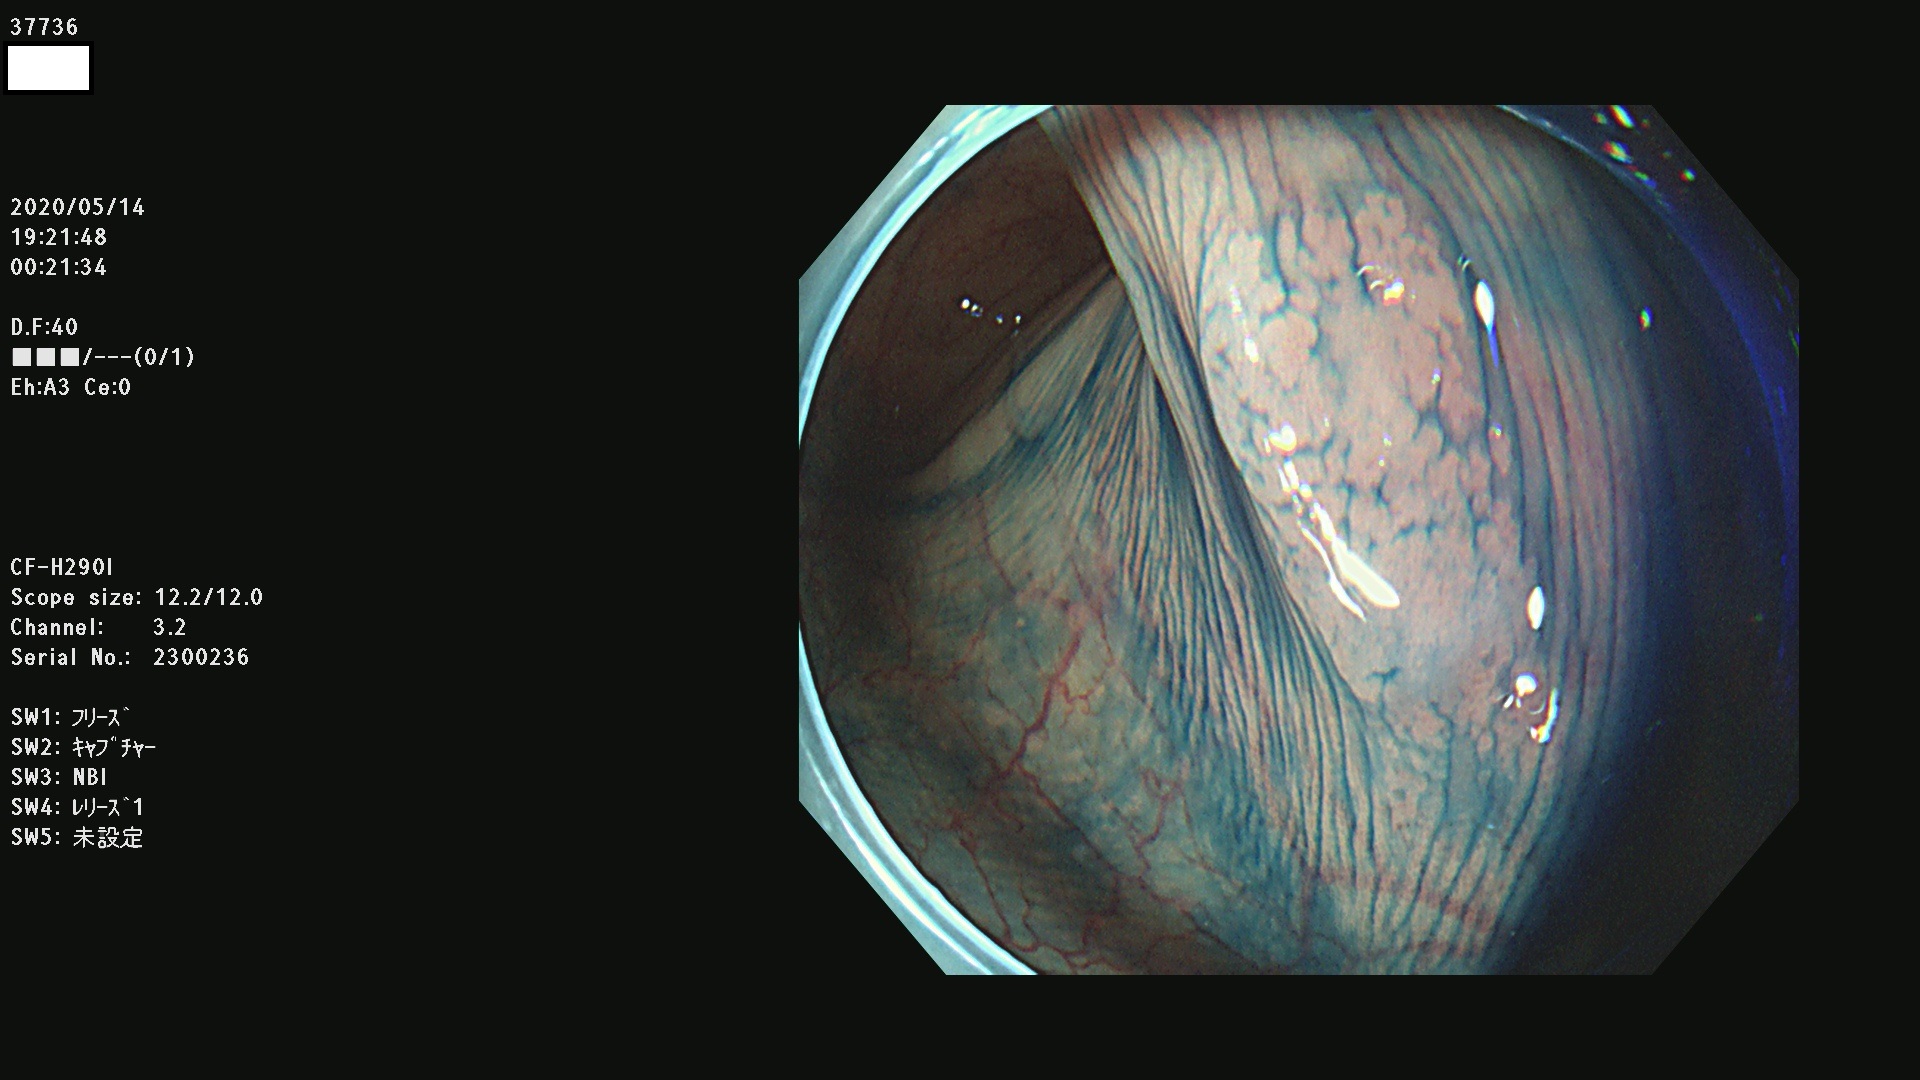

37700 37701 37702 37703 37704 37705 37706 37707(SSAPのみ) 37709 37711 37712 37715 37716 37717 37720 37722(SSAPのみ) 37724 37725 37726 37727 37728 37729 37731 37732 37733 37736(SSAPのみ) 37737 37739 37740 37741 37742 37744 37745 37748 37749 37750 37751 37752(SSAPのみ) 37753 37754 37755 37757 37758 37760 37761 37762(SSAPのみ) 37763 37764 37765 37766 37767 37768 37769 37771 37772 37774 37775 37776 37777 37780 37781 37782 37783 37784 37785 37787(SSAPのみ) 37788 37791 37792 37793 37794 37795 37799

発見困難で危険性の高い平坦型病変(上記100名より抽出)